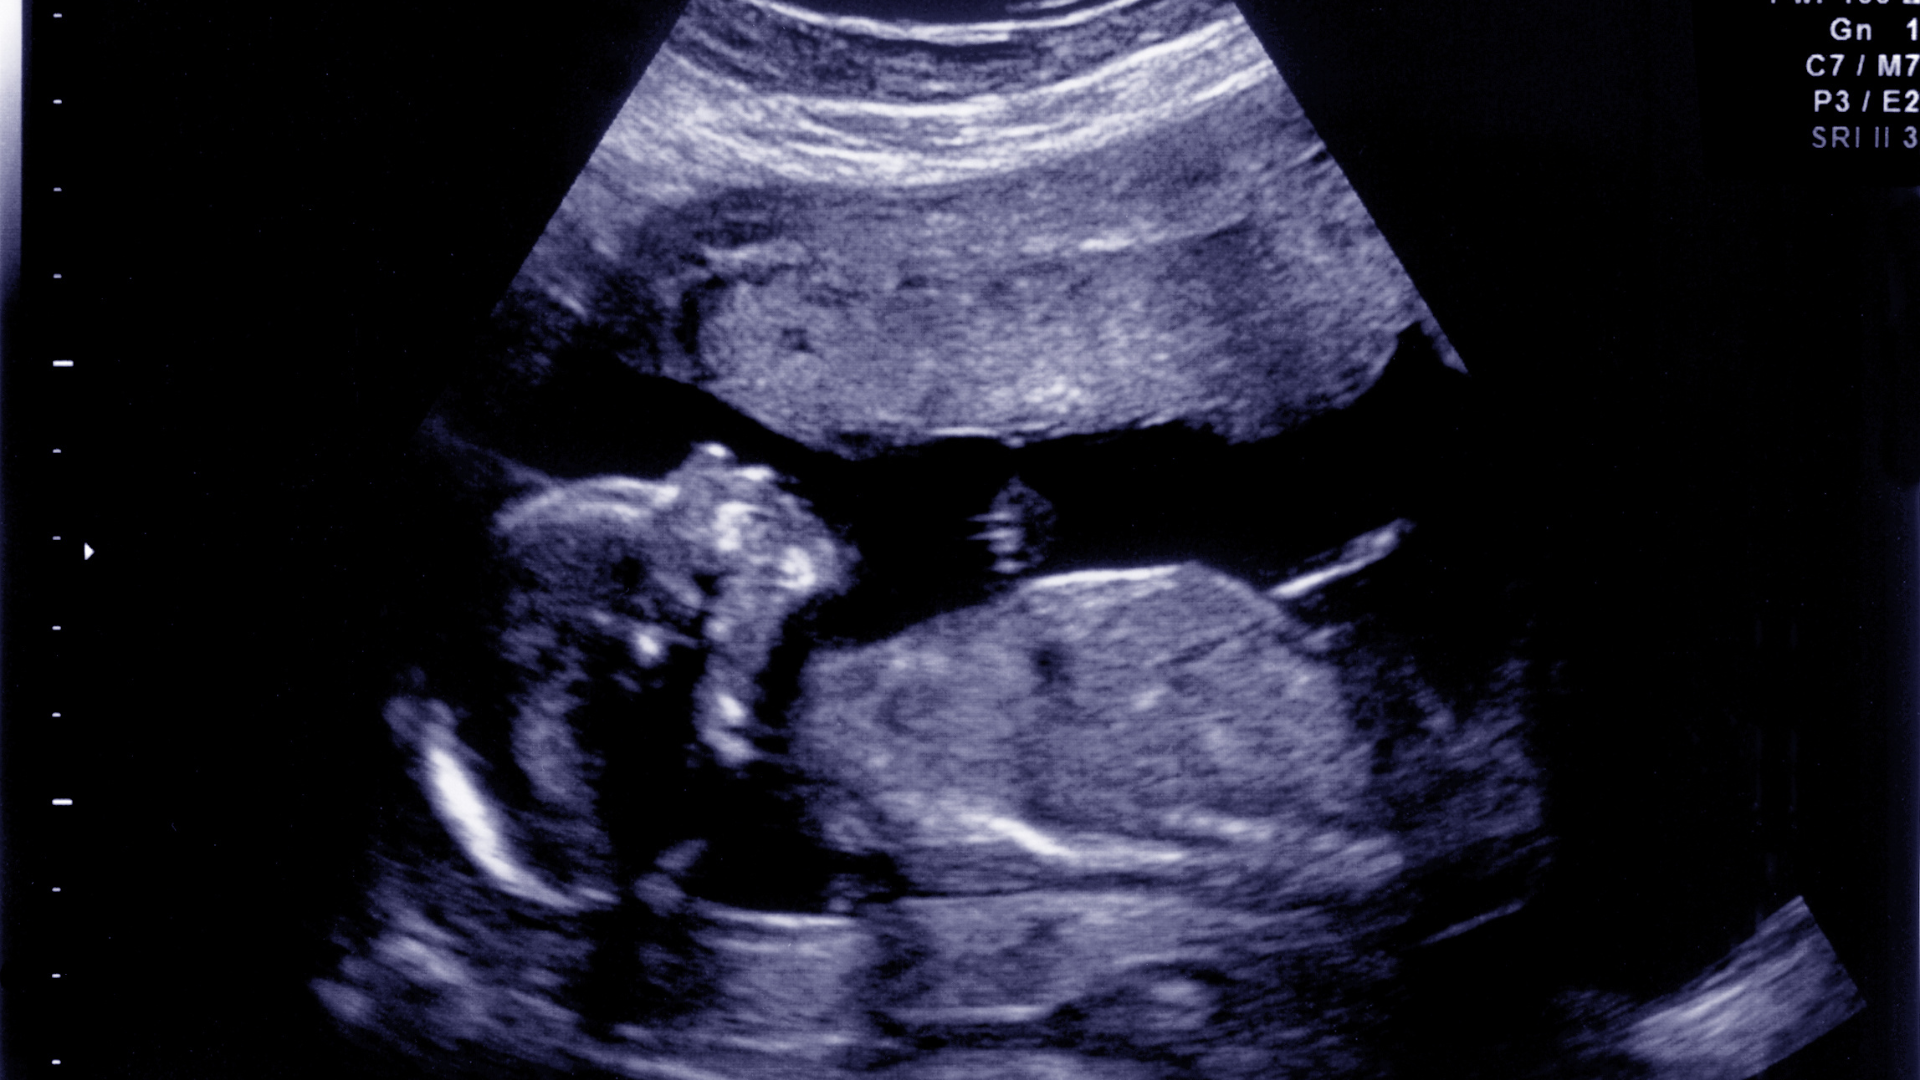

- Siêu âm đo kích thước các phần cơ thể thai.

- Đánh giá cân nặng ước tính theo tuổi thai.

- Theo dõi lưu lượng máu qua nhau thai và các mạch máu nuôi thai.

- Đánh giá nhịp tim, cử động thai và lượng nước ối.